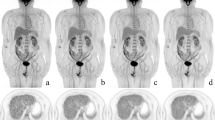

The mean weight of tissue samples used for quantification was 0.22 g (range: 0.08–0.45 g). The smallest detected tumour was less than 4 mm in size (Fig. 3). Correlation of radioactivity concentration in animal lesions, as determined by clinical PET and by ex vivo counting, was good for OSEM 3-D reconstruction (r 2 = 0.93) and somewhat better for PSF reconstruction (r 2 = 0.97) (Fig. 4a, c). Bland-Altman analysis demonstrated that the mean ratio between ex vivo quantitation and clinical PET quantitation was better with PSF reconstruction (Fig. 4b, d). PSF reconstruction improved T/B ratios (2.4 ± 0.9, p = 0.004) as compared to OSEM 3-D (1.4 ± 0.3). Figure 5 shows fused maximum intensity projection (MIP) and a coronal section of three mice bearing ovarian tumours imaged simultaneously. The CT component of the PET/CT acquisition was used for attenuation correction purposes but also allowed a better localization of the areas of increased tracer uptake, especially in the case of abdominal tumours. In the Lox-Stop-Lox (LSL) KrasG12D/+/Ptenfl/fl mice, which tend to have more abdominal fat than the nude mice, visualization of the ovarian tumours was particularly easy, thanks to the fatty areas around them, which appeared as low densities in contrast to the tumours, which are of tissular density (Fig. 5). In nude mice, which lack abdominal fat, image quality was poorer, especially in the case of haemorrhagic ascites (Fig. 3f).

Coronal slices for PET (a, d: PSF reconstruction; b, e: OSEM algorithm) and CT image (c, f) are shown for a mouse bearing subcutaneous tumour and imaged with 18F-FDG and for a mouse with an ovarian tumour involving the spleen and imaged with 18F-FLT. PET slices have been scaled to the same maximum. Note the improvement in T/B ratio when PSF reconstruction is used (a, d)

Three mice bearing spontaneous left ovary tumours were imaged on the clinical PET/CT. A fused MIP picture of the three mice imaged simultaneously (mouse 1, 2 and 3 at radial offset = −5, 0 and +5 cm) is shown together with selected coronal PET (PSF reconstruction) and CT slices and the necropsy specimen of one of these mice (white arrow)

Second, the CT component of the PET/CT acquisitions may be particularly useful in better localizing tumour uptake in the case of abdominal disease (Fig. 5), when physiological uptake in the gastrointestinal tract of the mice may be confusing. In nude mice, which lack abdominal fat, image quality was poorer, especially in the case of haemorrhagic ascites (Fig. 3). The image quality of the CT part of the PET/CT acquisitions may be improved by the use of novel IV contrast media, but the optimal injection protocol has to be determined for each animal model and mouse strain [29]. Contrast media protocols including both IV and intraperitoneal injections would also improve CT image quality and tumour detection in the abdomen [30].